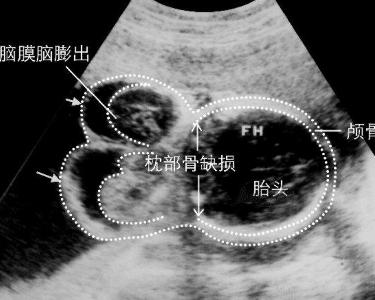

眼眶脑膜-脑膨出 (orbital meningoencephalocele)是由于颅内结构通过骨缺损疝入眶内引起的一种先天异常。单纯的脑膜疝出,内含脑脊液,形成囊性肿物名脑膜膨出(meningocele),脑膜伴有脑组织疝出的名脑膜-脑膨出。